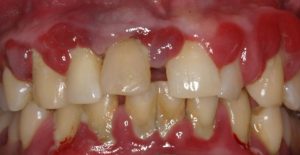

Gingivitis

Gingivitis is the first stage of periodontal disease. Plaque and its toxin by-products irritate the gums, making them tender, inflamed, and likely to bleed.